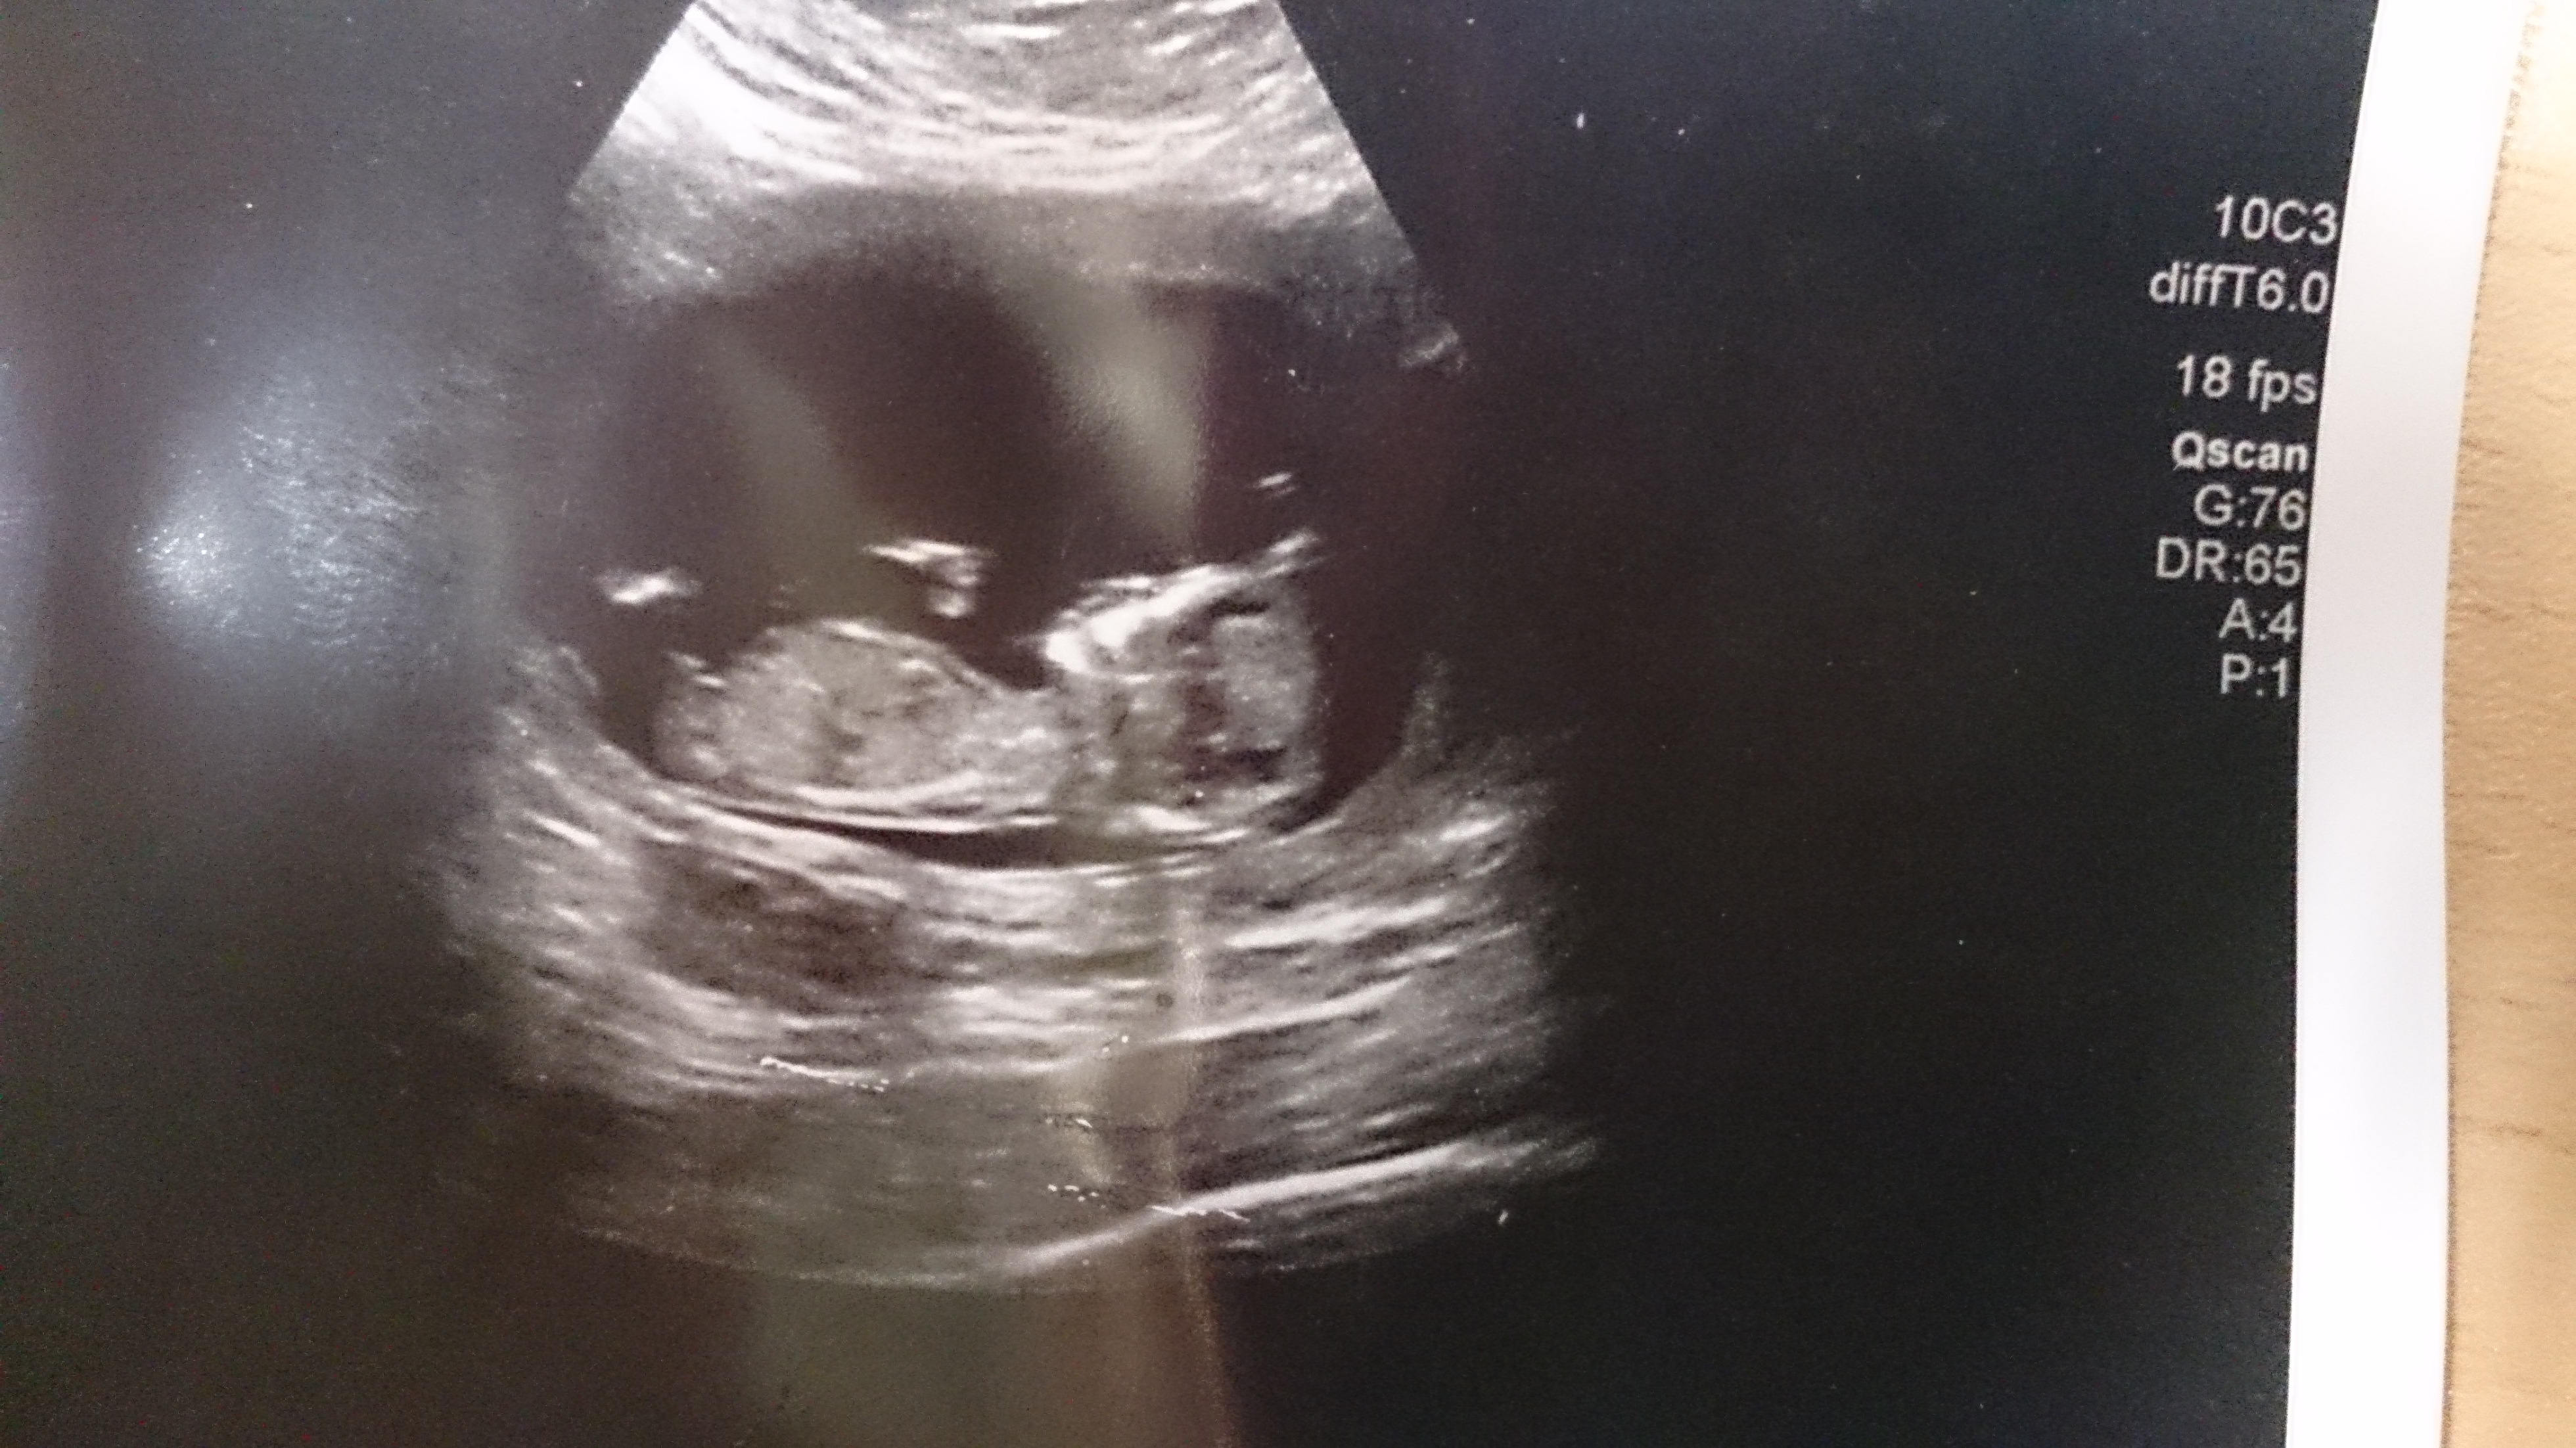

Please can you help me take a guess? We've already a little girl so tried to sway boy but I'm not sure, what do you all think? Thank you in advance xxx

If what I can see in the first pic is the nub, then it's a boy. But the second pic doesn't tell much. Good luck!

Nice stacked nub in first pic. Looks boyish :)